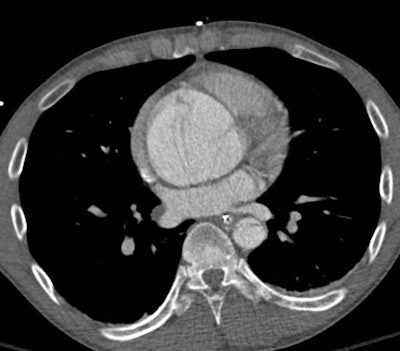

A 33-year-old man with Marfan syndrome and dilated aortic root. On the transverse images (A) the aorta measures 4.5 cm by 4.2 cm. When corrected for long axis (B) of the aorta, the aorta measures 3.9 cm by 4.2 cm. Measurements obtained orthogonal to the long axis of the aorta allow for consistent sizing and accurate risk assessment. Volume rendered image shows the root dilatation with mild effacement of the sinotubular junction (see below). This phenotype is sometimes referred to as annuloaortic ectasia, a characteristic finding of Marfan syndrome. Additional axial and coronal images of aortic dilation are provided (see below). All images courtesy of Sanjeev Bhalla, MD, and Mensur Koso, MD.